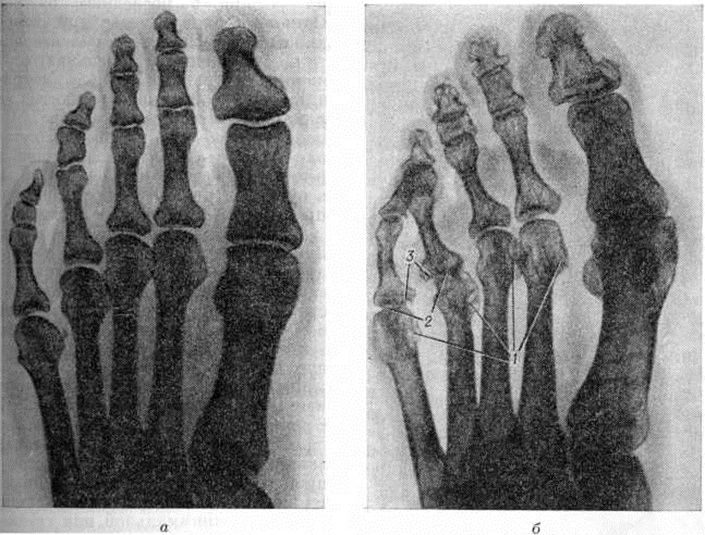

Рентгенодиагностика. В задачи рентгенодиагностики входит, помимо распознавания болезни, также оценка характера, тяжести и распространённости изменений костно-суставного аппарата, определение стадии, а при повторных исследованиях оценка эволюции заболевания. Наиболее распространённой методикой рентгенологическое исследования является стандартная рентгенография суставов. Более детальное изображение структуры кости можно получить, используя безэкранную рентгенографию. Томография (смотри полный свод знаний) при Ревматоидный артрит применяется крайне редко и имеет лишь вспомогательное значение. Поскольку наиболее характерные для Ревматоидный артрит рентгенологическое изменения обнаруживаются у взрослых в кистях и дистальных отделах стоп, а у детей, кроме того, и в шейном отделе позвоночника, эти области исследуют в первую очередь. Динамика рентгенологическое изменений при Ревматоидный артрит отличается медленным темпом, что делает излишним частое повторение исследования.

Продолжительность рентгенонегативного периода при Ревматоидный артрит значительно варьирует и чаще всего составляет от нескольких недель до 1—2 месяцев Ревматоидному артриту свойственны симметричность изменений суставов и склонность этих изменений к прогрессированию. Прогрессируют выявляемые рентгенологические изменения неравномерно, ускоряясь при обострениях болезни и замедляясь, вплоть до полной стабилизации, в периоды ремиссий. У ряда пациентов не отмечается корреляции между клинические, течением болезни и прогрессированием рентгенологическое изменений, в частности рентгенологическое картина может ухудшаться при отсутствии клинические, признаков активности ревматоидного артрита.

При Ревматоидный артрит обнаруживаются разнообразные рентгенологическое симптомы, ни один из которых нельзя считать патогномоничным. Ранние рентгенологическое изменения при Ревматоидный артрит являются неспецифичными, так как свойственны всем артритам (смотри полный свод знаний), и характеризуются утолщением мягких тканей в области поражённых суставов и околосуставным остеопорозом (смотри полный свод знаний). На ранней стадии более чем у половины больных Ревматоидный артрит отмечаются также кистовидные просветления в ближайших к суставам участках костей.

В дальнейшем присоединяется сужение суставных щелей, эрозии костей, подвывихи и вывихи (рисунок 7, 8). Часто на фоне описанных изменений на краях суставных поверхностей формируются остеофиты — проявление вторичного артроза. Тяжёлое ревматоидное поражение суставов может приводить к их анкилозированию; в случаях особо неблагоприятного течения возможен остеолиз ближайших к суставам отделов костей (рисунок 9). Как редкие рентгенологическое симптомы встречаются периоститы (смотри полный свод знаний), асептические остеонекрозы (смотри полный свод знаний: Остеохондропатия).

На основании рентгенологическое изменений суставов выделяют стадии Ревматоидный артрит Из многочисленных схем наиболее известна схема Стайнброккера, согласно которой выделяют 4 стадии ревматоидного артрита. К 1-й стадии относят случаи с околосуставным остеопорозом (смотри полный свод знаний), но без сужения суставных щелей и эрозии костей. Если к остеопорозу присоединяется сужение суставных щелей, то это соответствует 2-й стадии. Наличие эрозий костей указывает на 3-ю стадию, а костного анкилоза — на 4-ю стадию. Ларсен (A. Larsen, 1974) предложил более детализированную оценку, выделив 6 стадий, и дал для каждого сустава отдельную схему, отражающую местные особенности проявлений Ревматоидный артрит